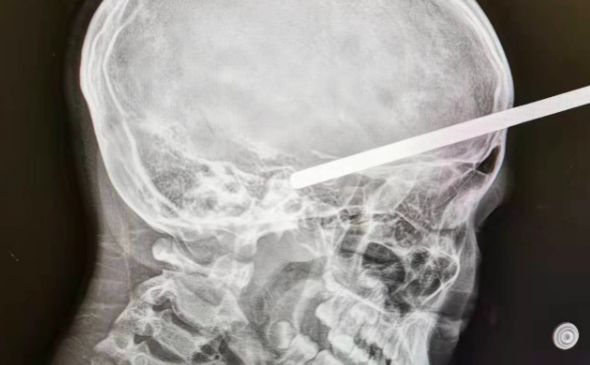

▲鐵棍插腦門。(圖/翻攝自澎湃新聞)

據《澎湃新聞》報導,10歲的女童靜靜(化名)2日下午3時,與母親、阿姨一起逛百貨公司,不料她突然腳底打滑,身體向前45度撲倒,迎面正好撞上貨架,貨架上懸掛商品的一根細長圓柱形空心鐵棍,直直插入靜靜的腦子裡。